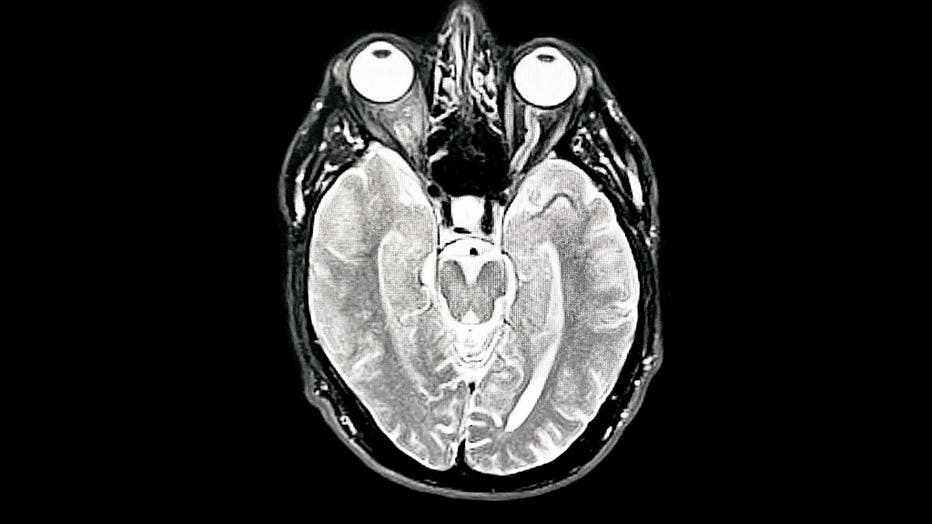

A brain scan image showing the cortex and deep brain structures. A new study finds that SuperAgers—people over 80 with exceptional memory—have thicker cortical regions and unique neurons that may protect against Alzheimer’s. (Photo by Peter Dazeley/Getty Images)

- SuperAgers have a thicker anterior cingulate cortex, a brain region tied to emotion, motivation, and decision-making.

- They show little to no thinning of the cortex, a typical sign of aging.

- SuperAgers have more von Economo neurons, specialized cells linked to social behavior, and larger entorhinal neurons critical for memory.